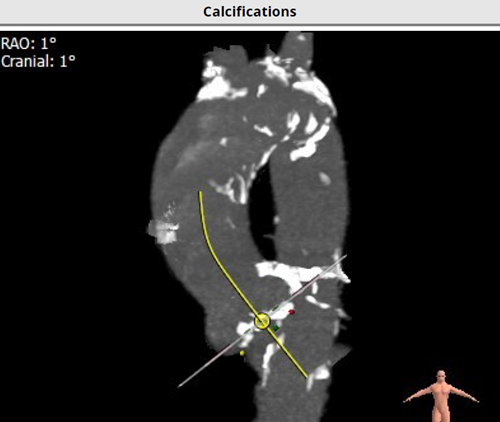

第二阶段:经导管主动脉瓣置换术。经导管主动脉瓣置换术需要在数字减影血管造影系统(DSA)下完成,手术团队还是通过原来的肋间切口,完成了穿刺,置入导丝和鞘管,球囊预扩张,瓣膜定位,释放瓣膜,球囊后扩张等一系列标准化流程,为患者植入一枚人工主动脉生物瓣膜。

经导管主动脉瓣置换过程